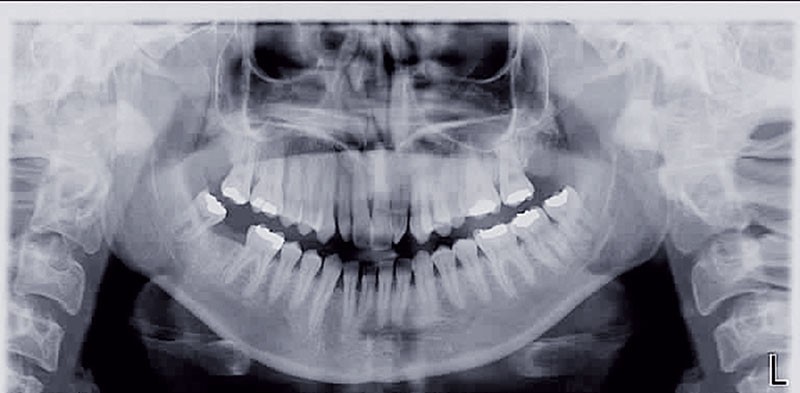

• anomalie de la forme d’arcade maxillaire, 47, 18 et 28 sont absentes. (fig. 1 à 8), 48 est positionnée très postérieurement, quasiment au niveau de la branche montante (fig. 9 et 11).

Après assainissement parodontal, un traitement par expansion maxillaire avec vestibuloversion des incisives supérieures et mésialisation de 48 en lieu et place de 47 a été choisi. Il a été décidé d’extraire 38. Afin de permettre une reconstitution prothétique pour compenser la microdontie de 12 il est prévu de laisser un espace de part et d’autre de celle-ci, équivalent au diamètre mésio-distal de 22 soit 6,5 mm.